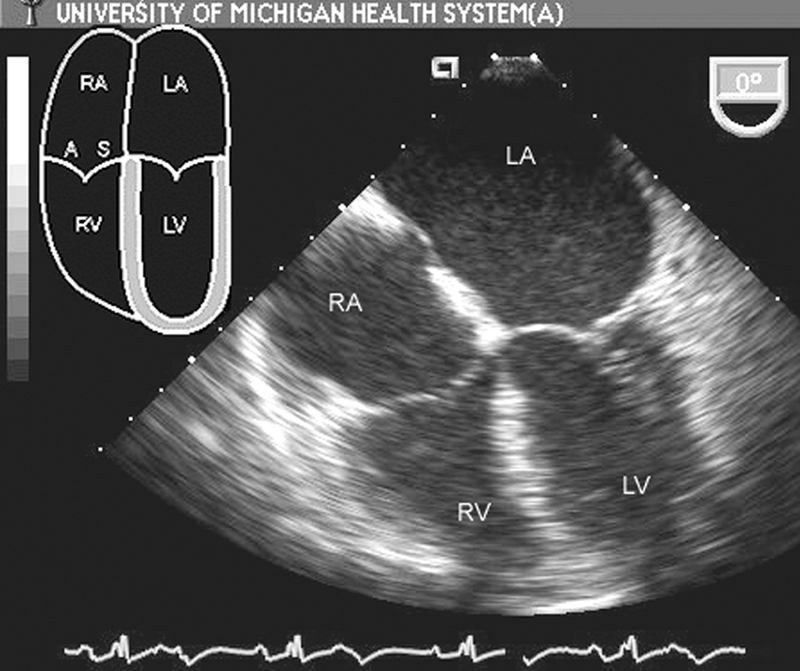

فحوصات تشخيصية لبعض امراض القلب والشرايين التاجية